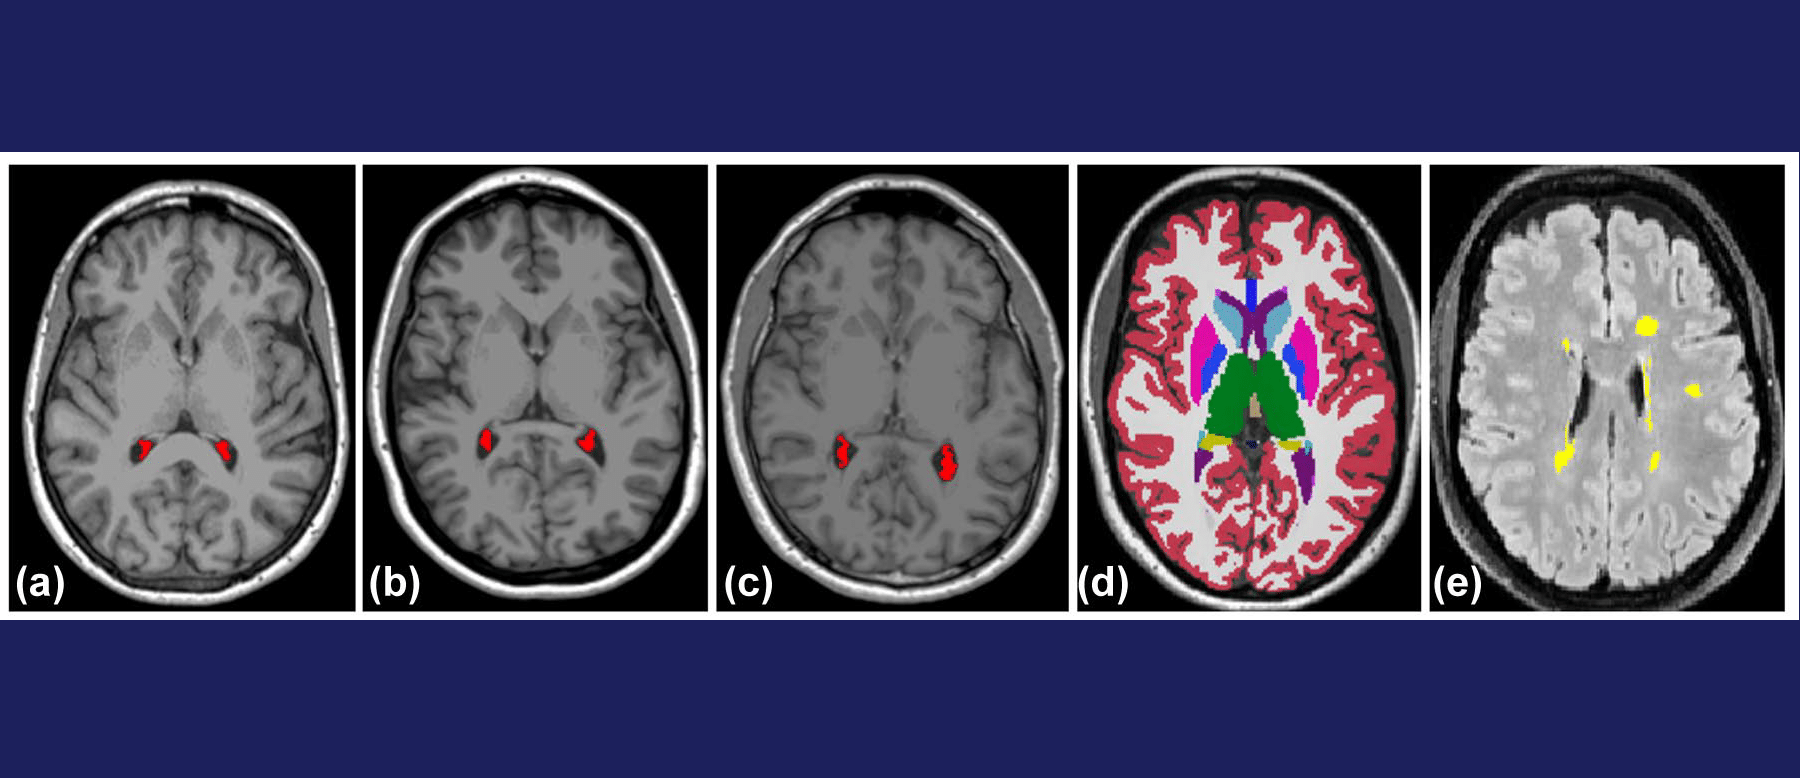

Purpose of the Review This review aims to provide the most up-to-date evidence on MRI biomarkers in multiple sclerosis (MS). MRI is the most

Purpose of the Study The goal of this study was to see whether people with Radiologically Isolated Syndrome (RIS)—a condition where brain scans show

This study explores the potential of low-field (64 mT) portable MRI (pMRI) as a diagnostic tool for identifying dissemination in space (DIS) in patients presenting with

Purpose of the Study The purpose of this study was to determine how often new lesions appear in the cervical spinal cord without any